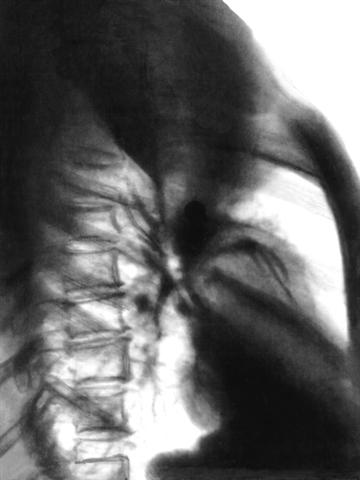

Рис. 2б). Рентгенограмма грудной клетки при ателектазе верхней доли правого легкого (правая боковая проекция): верхняя доля правого легкого уменьшена в объеме, гомогенно затенена.